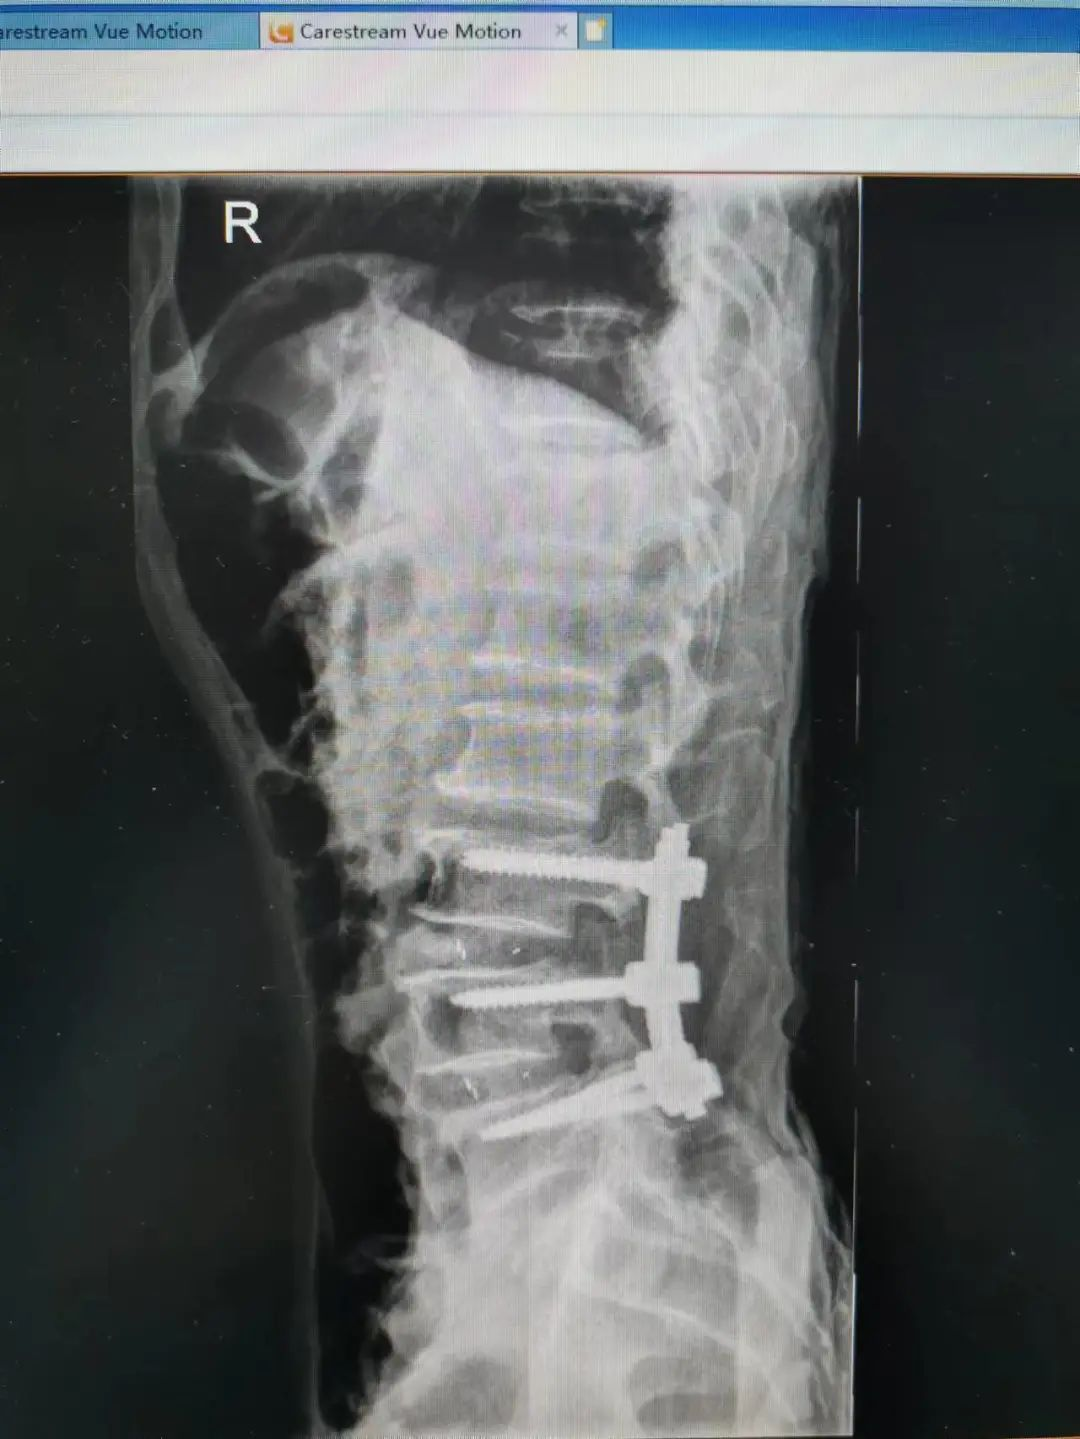

由于楊先生的病情嚴重,需住院治療。楊先生入院后,瀘州市中醫(yī)醫(yī)院骨傷二科科主任楊陳一制定了手術計劃,決定脊髓型頸椎病的手術從前路切開減壓,頸3/4 、頸4/5、 頸5/6、 頸6/7椎間盤切除,椎間融合,鋼板內固定術手術,而腰椎管狹窄癥經后路切開減壓,腰3/4、腰4/5椎同盤動除,椎間融合、釘棒系統(tǒng)內固定術。

楊先生術后拍片